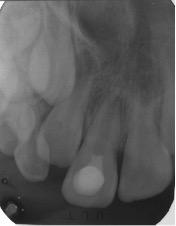

La secuencia de tratamiento se realizó en 2 sesiones: la primera sesión se basó en la desinfección del conducto radicular, utilizando como agente irrigante inicial 20ml de hipoclorito de sodio al 2,5% y 10ml clorhexidina al 2%, como irrigante final, intercalando la irrigación con 10 ml de cloruro de sodio, para evitar la formación de precipitados;2,5,15,18,19 luego el conducto radicular fue secado con conos de papel estériles. Finalmente, en el conducto radicular se colocó la pasta antibiótica 3Mix (Figura 3-5), mezclado previamente según las indicaciones de Quintana y cols.22 La segunda sesión, se realizó a las 2 semanas,22 lográndose la inducción del sangrado (formación del andamio) y colocándose una barrera cervical de MTA. El éxito del tratamiento de revascularización pulpar también depende en gran parte de una adecuada reconstrucción y sellado a nivel coronal, en este caso se realizó utilizando materiales ionoméricos y resinosos (Figura 6-10).

Figura 3: Apertura cameral con piedra diamantada redonda a nivel de la cara palatina. Conductometría con lima K N° 35 en una longitud de 17 mm. Control radiográfico.

Figura 4: Preparación biomecánica con lima K N°35, en una longitud de 12 mm. Sólo a nivel cervical para mejorar visibilidad y el acceso al conducto radicular. Irrigación inicial con hipoclorito de sodio al 2.5% y 10ml clorhexidina al 2%, como irrigante final, intercalando la irrigación con 10ml de cloruro de sodio.

Figura 5: Aplicación de Pasta 3 Mix intra conducto con lima K No 25. El sellado de la entrada del conducto radicular se realizó con pasta de eugenato + ionómero de vidrio por un período de 15 días. Control radiográfico.